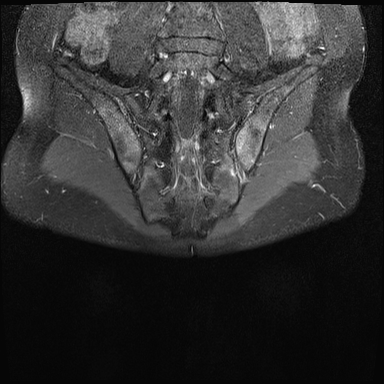

MRI

MRI chuỗi xung T1W sau tiêm thuốc tương phản từ của cùng bệnh nhân cho thấy bờ khớp cùng chậu không đều do bào mòn.

Có ngấm thuốc ở xương dưới sụn và phù nề tủy xương.

Không có tràn dịch khớp.

Thuốc tương phản từ tiêm tĩnh mạch không nhất thiết phải sử dụng để chẩn đoán viêm khớp cùng chậu.

Cuộn qua các hình ảnh MRI và so sánh với các dấu hiệu trên X-quang (hình ảnh cuối cùng).